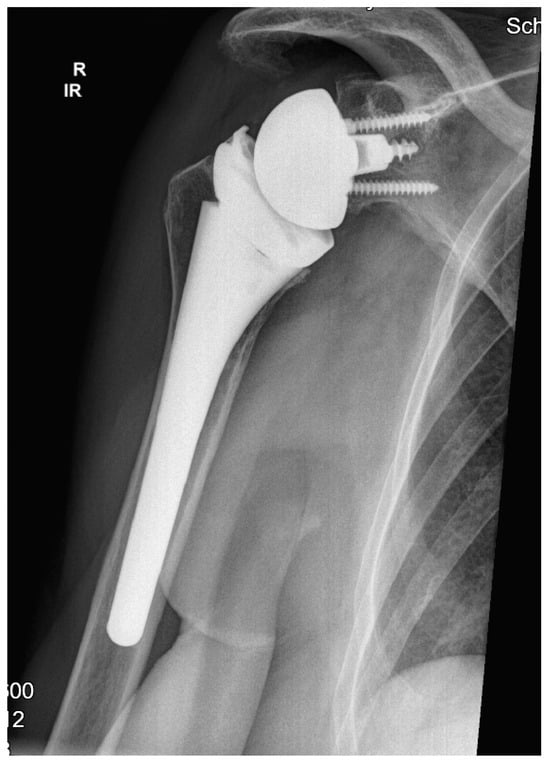

All patients were treated with RSA using the Univers Revers prosthesis with a 135° NSA (Arthrex, Naples, FL, USA; Figure 1) combined with the Universal Glenoid (Arthrex, Naples, FL, USA). The design of this prosthesis is based on the usage of a rectangular metadiaphyseal locking stem that is combined with a metaphyseal cup which be used centered or with either 2 mm left or right offset according the humeral diaphysis. This humeral inlay design is further completed by the usage of a standard or constrained +3 mm or +6 mm humeral polyethylene liner that offers adaptation to the glenosphere diameters’ different concavity depths (jump heights) from 9.8 mm (36 mm standard) to 13.9 mm (42 mm constrained) and following stability ratios of 193–194% using a standard liner as well as stability ratios of 277–300% using constrained liner designs [].

Figure 1.

Example at the five-year follow-up after reverse shoulder arthroplasty with 135° NSA and a cementless metadiaphyseal fixation stem (Univers Revers, Arthrex, Naples, FL).